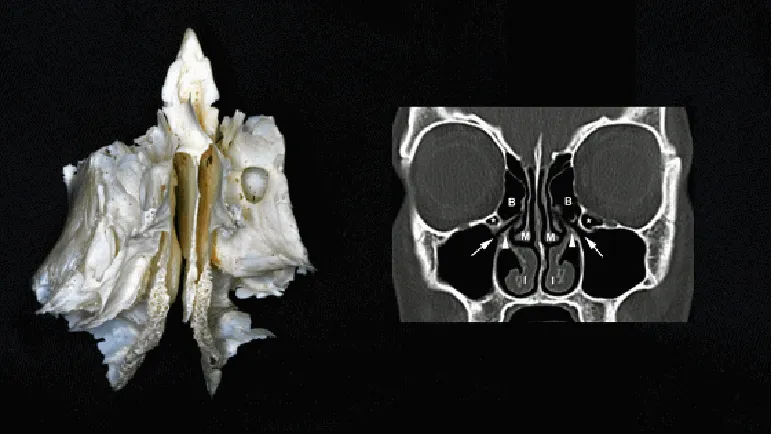

1.解剖结构:鼻窦为鼻腔周围颅骨中的一些含气空腔,左右成对,共4对,依其所在颅骨命名,为上颌窦、额窦、筛窦和蝶窦。筛窦尤其重要,因为它们靠近眼眶。视神经、眼动脉和其他重要结构穿过视神经管和眶上裂,与筛窦相邻。筛骨是颅底中最小但居C位的骨,也是孔洞最多的骨。筛骨迷路位于筛骨两侧,外表面为眶的内侧壁,称为眶板或筛骨纸样板,呈块状部分则含多个小房,即筛窦。

▼筛骨,它实质上是两块骨在中线由筛板连接而成。

筛窦解剖:整个筛窦与眼眶之间仅由极薄的骨板隔开,其中尤以纸板最薄,当眼眶骨折时,此处容易爆裂。筛窦的解剖变异,如纸样板变薄或眼眶靠近筛窦气房,会增加手术中眼眶并发症的风险。外科医生应该意识到这些解剖变异,并在手术操作中小心谨慎,以避免损伤眼眶结构。